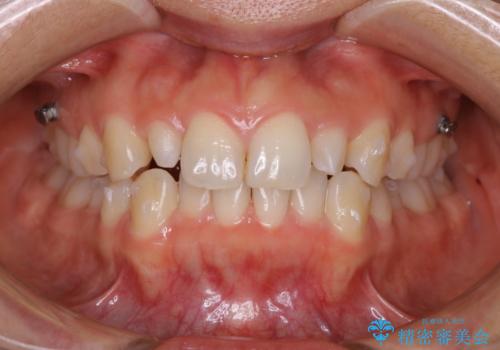

- インビザラインFULL

- 上の前歯が大きい事と下の前歯のがたつきを気にされてご相談にいらした方です。上の2番目の歯が矮小歯であったため、矯正治療にて歯のスペースを作った後、矮小歯には被せ物をして前歯のバランスを整えました。